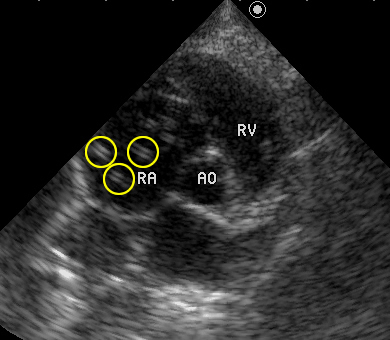

猫のフィラリア症の心エコー検査。

黄色の円で囲まれた、白い「=」の形をしているのがフィラリアの中虫です。